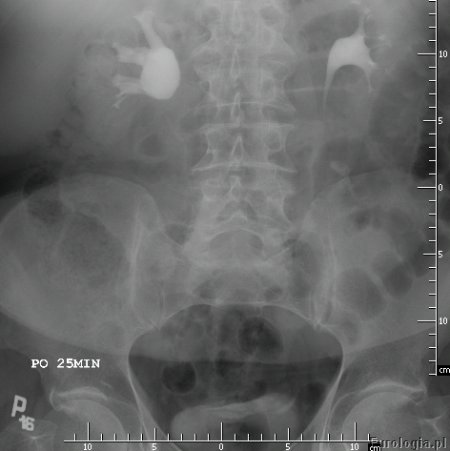

Zwężenie połączenia miedniczkowo - moczowodowego